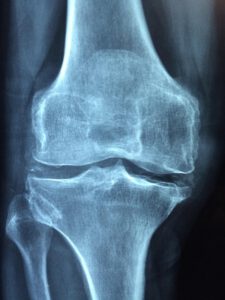

Bild von Dr. Manuel González Reyes auf Pixabay

Osteoporose zählt laut Weltgesundheitsorganisation (WHO) zu den zehn häufigsten Volkskrankheiten weltweit. Jede zweite Frau und jeder fünfte Mann ist im Laufe des Lebens betroffen. Die VHS Lippe-Ost bietet am Freitag, 13. Februar 2026, einen Vortrag in der Schlossparkschule Schieder-Schwalenberg an, der über Ursachen, Vorbeugung und Behandlungsmöglichkeiten bei Osteoporose informiert.